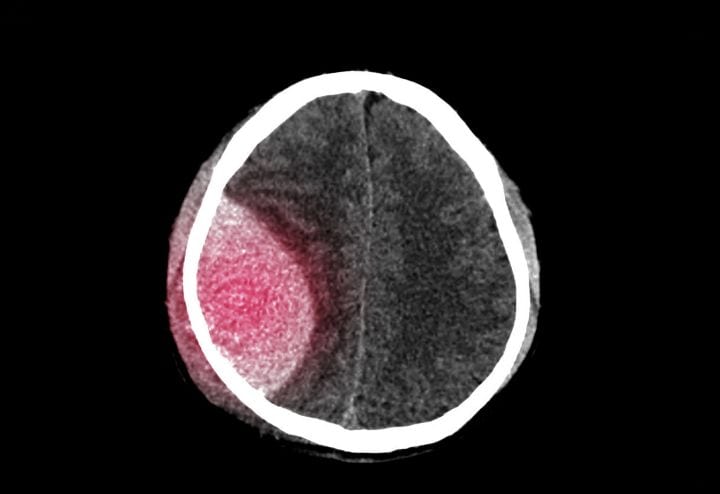

- Επισκληρίδια, υποσκληρίδια και ενδοεγκεφαλικά αιματώματα